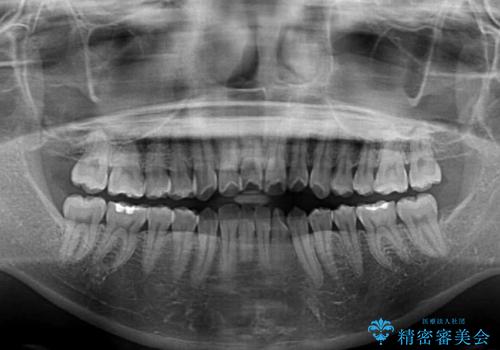

- 口元の突出感と口の閉じにくさを気にして来院された患者様です。

上下左右第一小臼歯4本を抜歯し、ワイヤー装置にて口元を引っ込めるよう矯正治療を行うこととしました。

2年~2年半が治療期間の目安でしたが、順調に治療が進み、1年9か月で満足のいく歯列となりました。